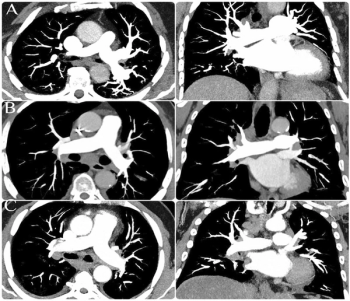

In a study of over 20,700 people, researchers found that artificial intelligence (AI) analysis of body composition measurements via lung cancer screening computed tomography (CT) exams improves the prediction of mortality risks for lung cancer, cardiovascular disease, and all-cause mortality.